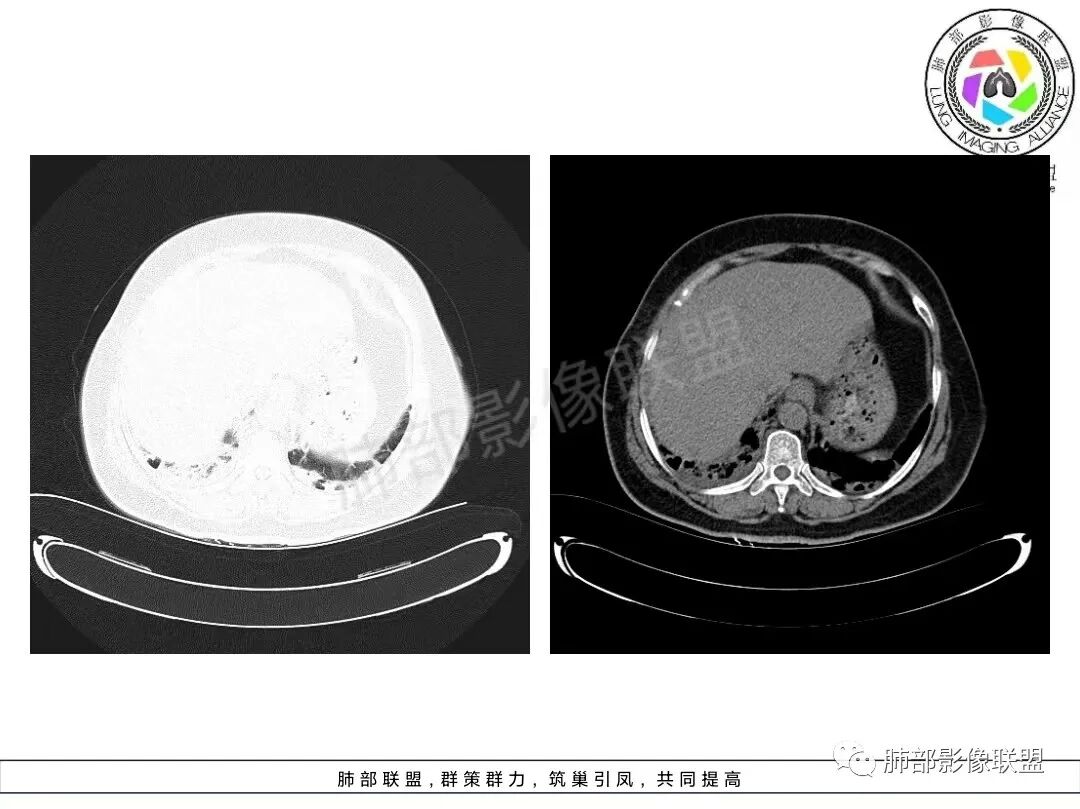

1、临床特点:70岁女性,务农。咳嗽咳痰伴气急20天。症状逐渐加重。有高血压病史。入院查体:体温37.5℃,急性面容。白细胞、CRP、红细胞沉降率升高。血糖高,CEA升高、余肿瘤标志物正常。ANCA检查阴性。血培养阴性,支气管灌洗液培养、真菌检测、抗酸杆菌均阴性。

2、影像特点:双肺胸膜下为主、多发斑片影、结节样实变影及磨玻璃样密度影,大部分病灶边缘平直、边界清,磨玻璃密度病灶内可见细网格影,部分病灶内可见支气管扩张表现,部分支气管直达远端,部分中断于病灶中部。部分病灶有侧向融合趋势。

3、病例小结:老年女性,咳嗽咳痰伴气急逐渐加重,入院后有低热。部分炎性指标升高,肺部片影,可以符合感染性病变,但是血培养、支气管灌洗液培养等检查无阳性表现。但仍影警惕隐球菌感染,患者临床表现相对轻微,胸膜下病灶,磨玻璃影等。

影像上双肺多发磨玻璃影及实行密度影,对称分布趋势,op样改变,结缔组织相关性疾病需要排除。临床上可进一步查皮肌炎相关指标、仔细进行体格检查看看患者皮肤等情况。